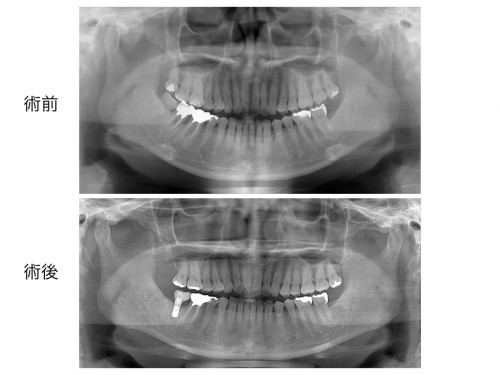

レントゲン写真ですが歯周病の重度の進行があります。

インプラント治療を行う際はレントゲンCTが必須です。

CTでインプラントの入る骨の厚みがあるのか調べます。

レントゲンCTを分析し、インプラント治療を行う位置を決めていきます。

その通りの位置にインプラント治療を行います。

位置がずれていたりすると見た目もおかしな歯になってしまいます。

想定していた位置にインプラント治療ができました。

レントゲン写真です。

噛み合わせもしっかり安定しています。

この様に事前にしっかりと計画を立て、無理のない治療を施術すると思い描いた通りのお口を作ることができるのです。